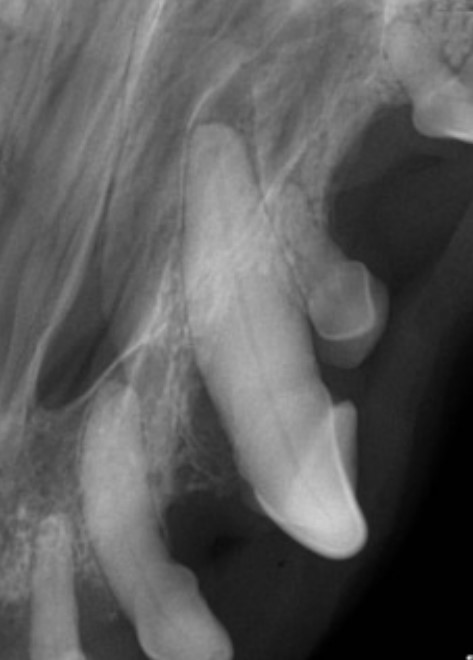

Figure 4: Canine tooth with a deep periodontal pocket before guided tissue regeneration \

Figure 5: Canine tooth after guided tissue regeneration. The periodontal pocket has been populated with bone and a new periodontal ligament space is present indicating regeneration of the periodontal ligament. (First premolar tooth has been extracted)

Teeth with deep pockets can often be saved by performing open root planing, followed by guided tissue regeneration to replace lost supporting bone. In guided tissue regeneration, bone-grafting material is placed in periodontal pockets and a resorbable collagen membrane is placed over the graft. The membrane prevents soft tissue from migrating into the pocket until new periodontal ligament and bone regenerates. These treatments are only suitable for some types of periodontal bone loss and a veterinary dental specialist needs to evaluate teeth with radiographs and an oral examination under anesthesia in order to determine if they are candidates for these procedures.